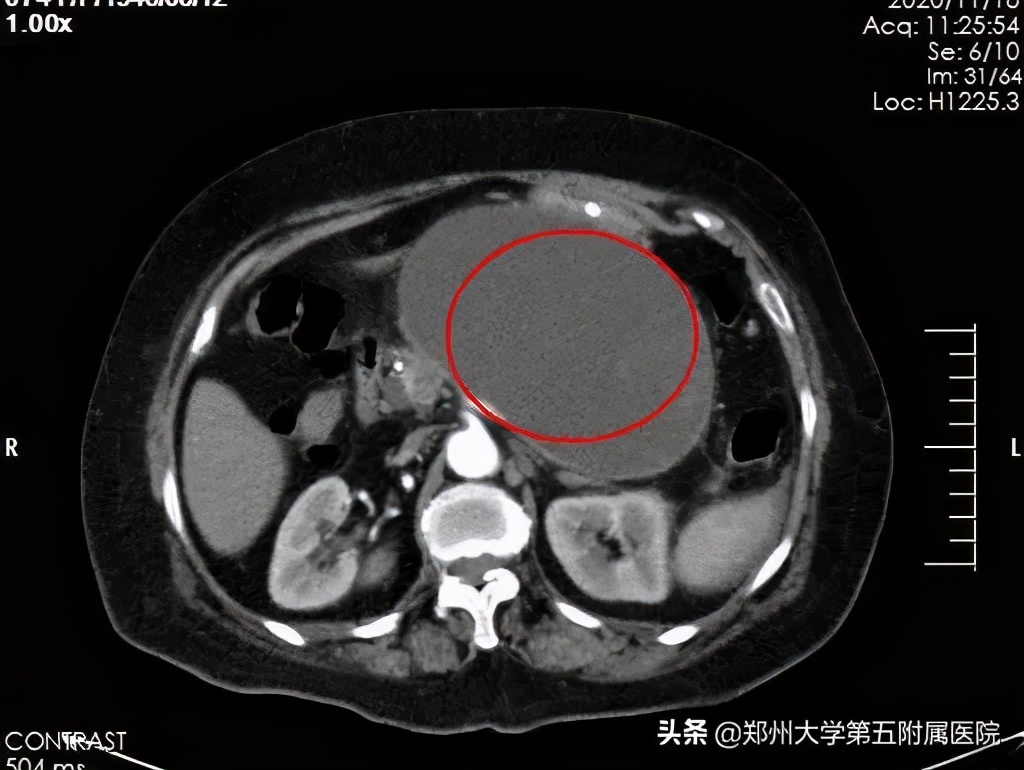

74岁的仇老太太今年8月底开始出现腹痛、腹胀、恶心、呕吐等症状,在当地医院确诊为“急性重症胰腺炎”。由于病情较重,辗转几个医院,治疗效果依然不满意,后来坏死的胰腺组织及渗出积液逐渐包裹形成了胰腺假性囊肿,观察8周胰腺假性囊肿逐渐增大,并出现了局部压迫症状,患者频繁恶心、呕吐,无法进食。后患者家属带她来到郑州大学五附院,查腹部CT提示胰腺体尾部巨大假性囊肿,大小近20cm。

在消化内镜中心主任郑权指导下,刘谦副主任医师先行超声胃镜检查,以确定囊肿的位置,大小,是否适合超声下穿刺置管引流,超声内镜显示囊肿15+cm,囊壁与胃壁距离小于1cm,病灶毗邻胃后壁,胃腔严重受压。在超声内镜引导下成功穿刺进囊肿,切开囊肿壁,大量脓液流出,囊肿明显缩小,后置入双猪尾支架和鼻囊肿引流管结束手术,术中引流囊液约1000ml。